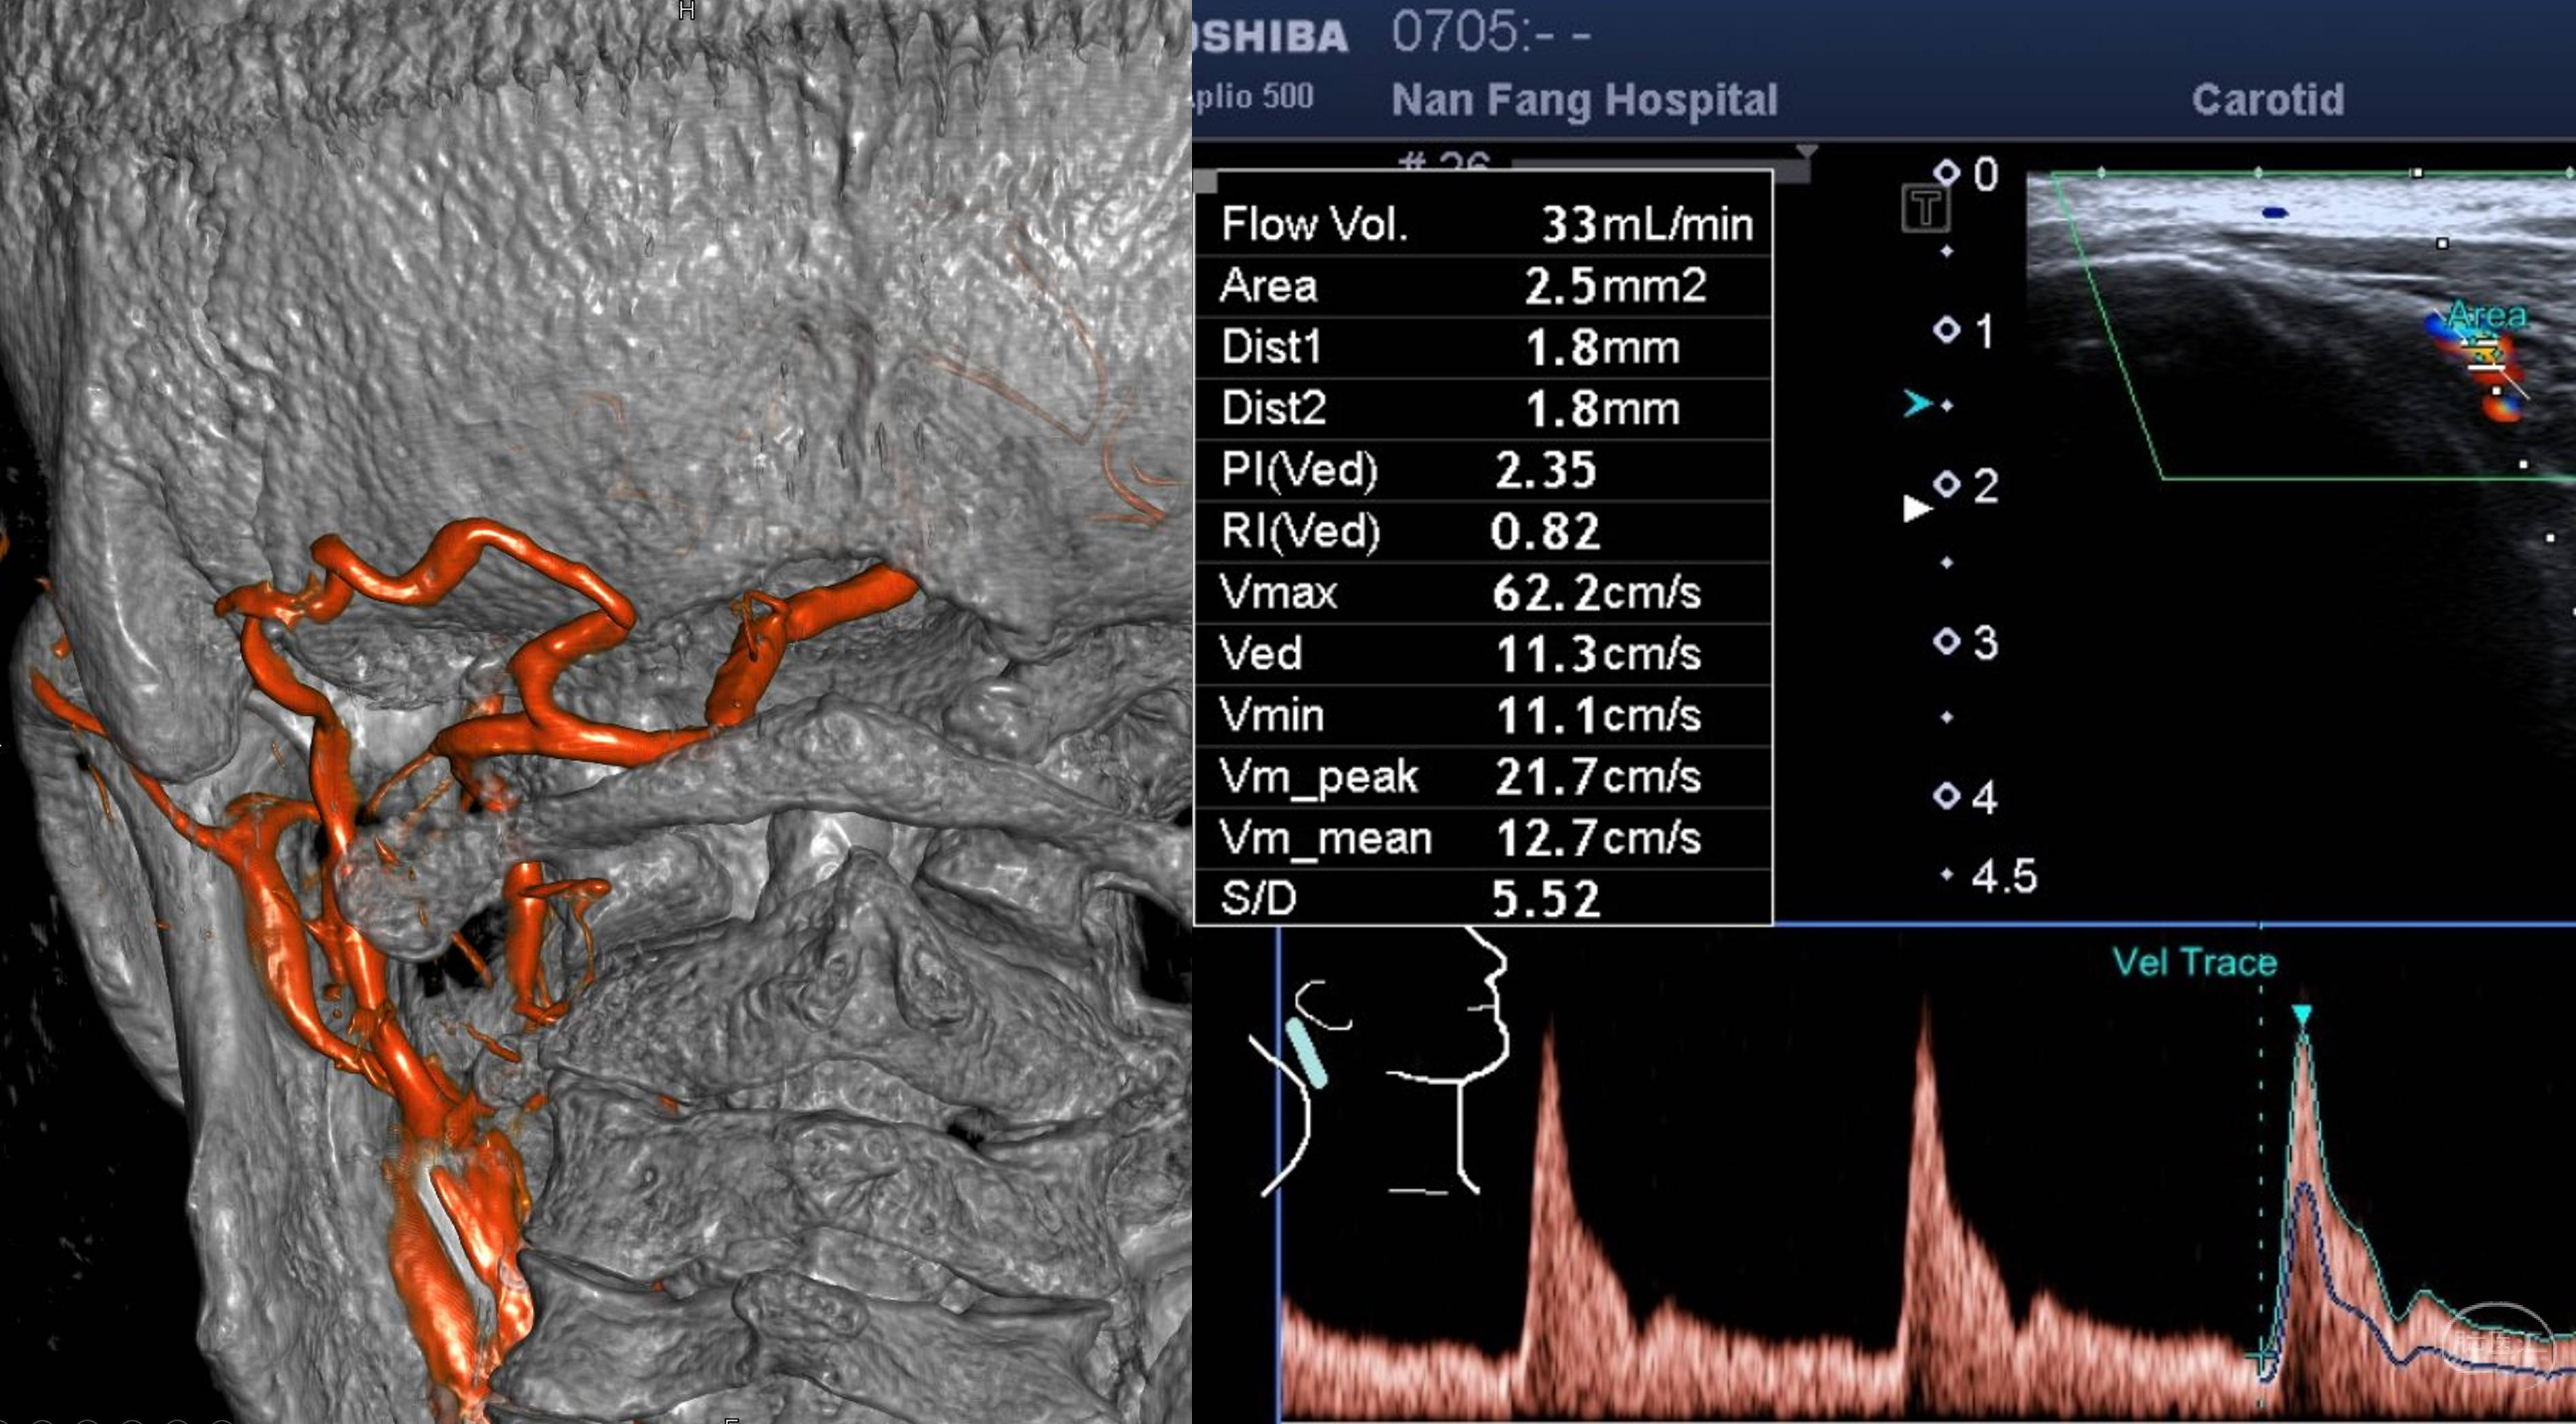

三维重建,提示骨性结构完好,OA-V3桥血管通畅,吻合口无狭窄。超声提示血流量33ml/min。